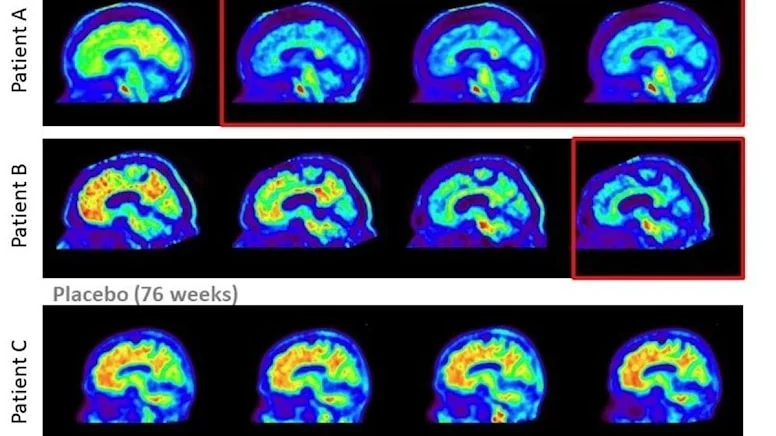

ABD merkezli ilaç şirketi Eli Lilly’nin geliştirdiği donanemab isimli ilacın “güçlü ve anlamlı” bir sonuç elde ettiği belirtildi. Şirket, yapılan klinik testler sonucunda elde edilen resmi verileri kamuoyu ile paylaştı.

Yapılan açıklamada şirketin geliştirdiği ilacı alan katılımcılarda hastalığının ilerleme riskinin yüzde 40 oranında azaldığı tespit edildi.

Donanemab isimli ilacın beyindeki plağa saldıran bir antikor olarak görev aldığı kaydedildi.